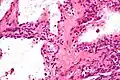

| Micrograph showing a pancreatic serous cystadenoma. H&E stain. | |

Pancreatic serous cystadenoma is a benign tumour of the pancreas.[2] It is usually solitary and found in the body or tail of the pancreas, and may be associated with von Hippel–Lindau syndrome.[2]

Pathologists classify serous cystic neoplasms into two broad groups. Those that are benign, that have not spread to other organs, are designated "serous cystadenoma".[5] Serous cystadenomas can be further sub-typed into microcystic, oligocystic (or macrocystic), solid, mixed serous-endocrine neoplasm, and VHL-associated serous cystic neoplasm. This latter classification scheme is useful because it highlights the range of appearances and the clinical associations of these neoplasms. Serous cystic neoplasms that have spread ("metastasized") to another organ are considered malignant and are designated "serous cystadenocarcinoma".